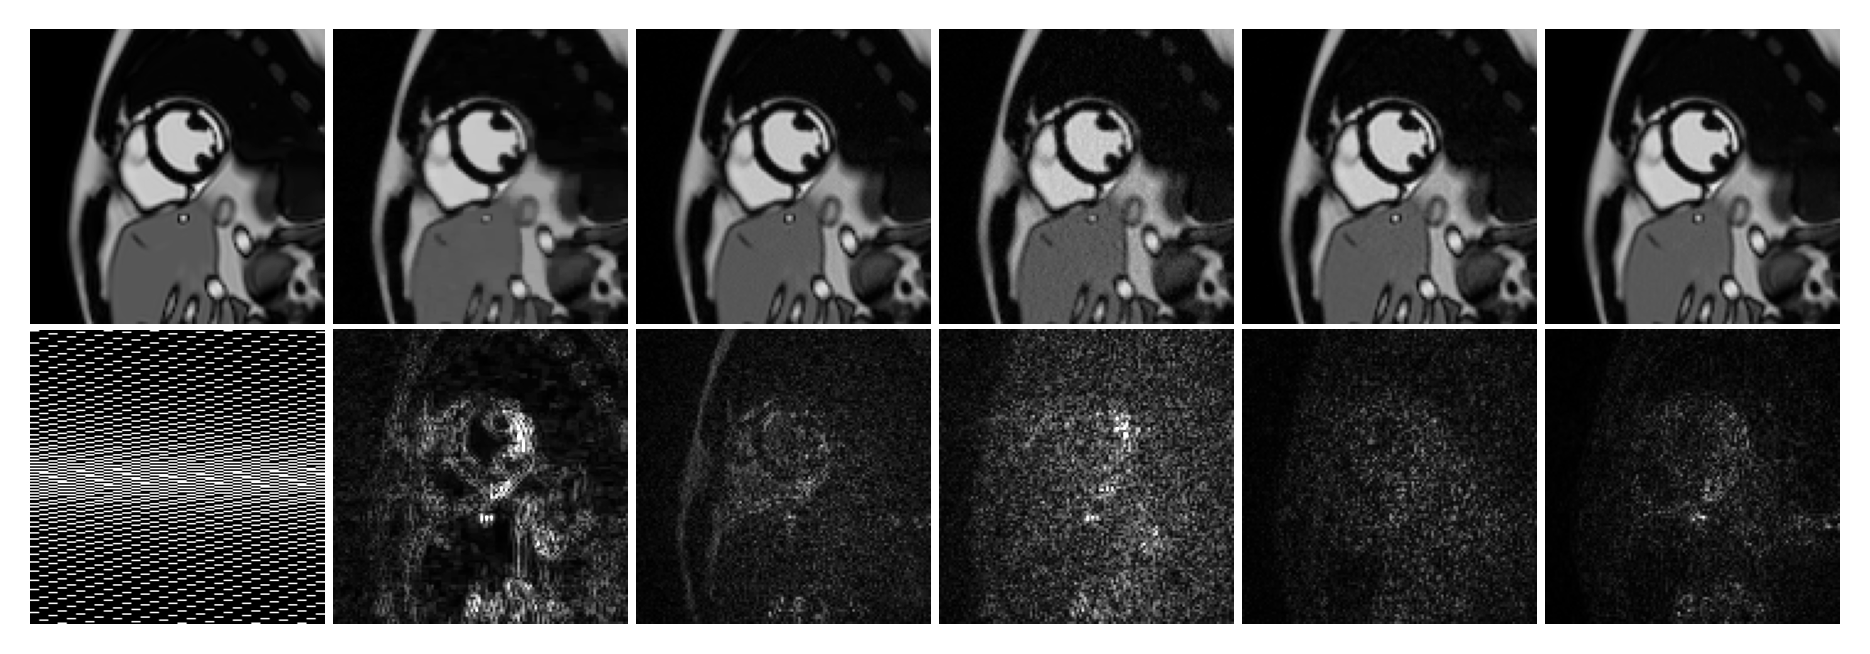

Refer to caption(b)TrueCSL+SDISCUSRefer to caption(a)Refer to captionRefer to caption

Fig.ย 2: (a) One of the dynamic code vectors {๐’›^t}t=1Tsuperscriptsubscriptsubscript^๐’›๐‘ก๐‘ก1๐‘‡\{\hat{\bm{z}}_{t}\}_{t=1}^{T} from image series with rotations (left), translations (middle), and rotations+translations (right). The number of non-zero entries matches the true dimensionality in each image series. (b) One representative frame from the image series with rotations+translations. The first image in the second row presents the sampling pattern (frames: left-right, phase-encoding: top-bottom, frequency-encoding: not shown), and the remaining images show error maps after fivefold amplification.